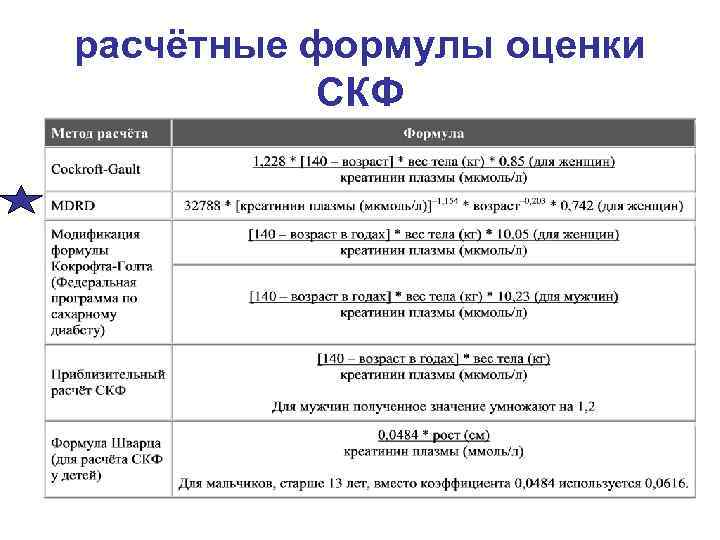

расчётные формулы оценки СКФ

расчётные формулы оценки СКФ